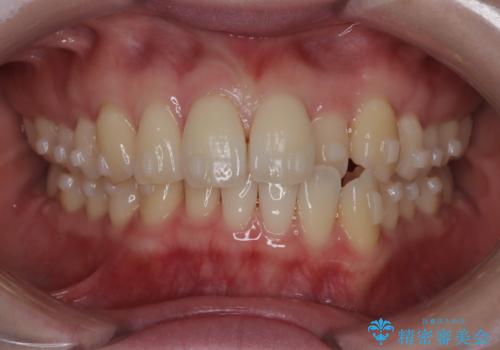

- 左上2の反対咬合(交叉咬合)をインビザラインを用いて治療しました。反対咬合は、歯列の不正咬合の一つであり、上の歯が下の歯よりも内側に位置する状態です。反対咬合は咀嚼や発音に影響を与えることがあります。

左上2の反対咬合をインビザラインで治療する際に、IPR(Interproximal Reduction)を行いました。 IPRとは、隣接する歯の間のエナメル質をわずかに削る手法で、歯の幅を減少させることによって歯列を整える技術です。